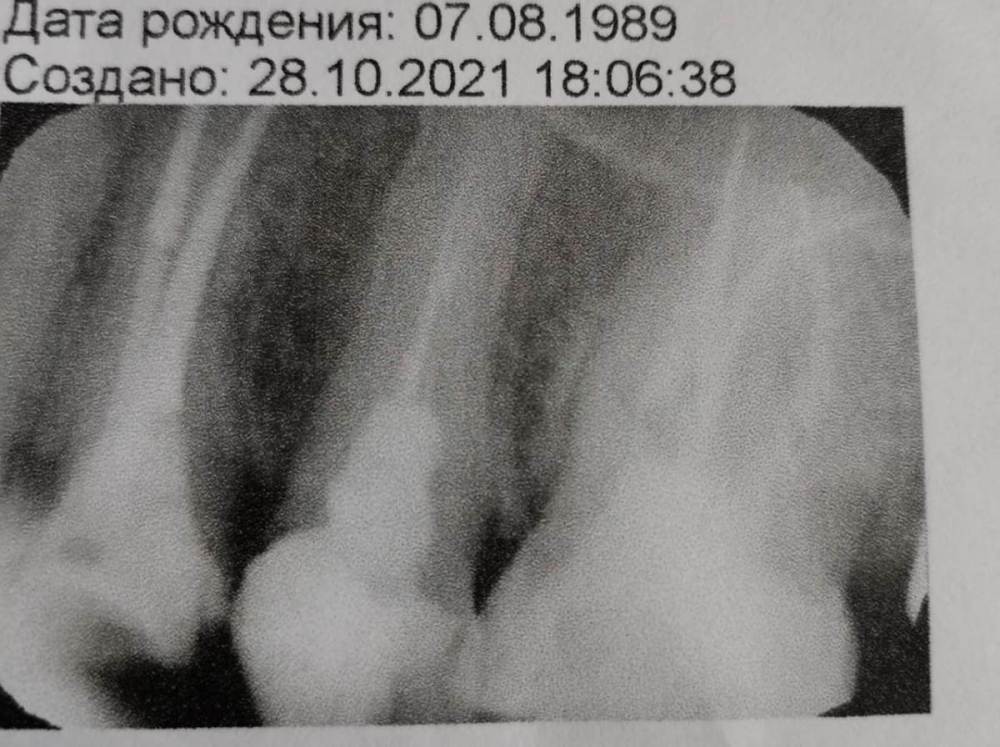

alena1504 Опубликовано 26 ноября, 2021 Поделиться Опубликовано 26 ноября, 2021 (изменено) Здравствуйте! В марте 2021 года делала имплант 27 го зуба, боль не проходила долгое время, списывала все на процесс приживления, обошла около 4 х имплантологов, все уверяли, что с имплантом все хорошо, болел сустав (и сейчас больно широко рот открывать) уже и лазером лечила и таблетками, и каппу специальную мне сделал ортодонт. Тогда было принято решение заменить пломбу на 26 м зубе, так как под пломбой уже оказывается образовался глубокий кариес, врач принял решение удалить нервы и почистить каналы, все сделали, а боль не проходит, закладывала и антибиотик и калосепт, все также. Тогда она сказала ехать в клинику где лечат под микроскопом. Вот тогда врач сказал, что его коллега когда чистила каналы, а один канал у меня изогнутый, переусердствовала и сделала перфорацию и теперь, когда он пытается пройти мой изогнутый канал, проваливается в эту перфорацию. Последний раз вот он около часа просто пытался пройти канал, но говорит он склерозированный и плюс эта перфорация. Говорит нужно делать резекцию. Но на корнях воспаления нет. Хотя боль постоянная, не прекращающаяся, ноющая, отдает периодически то под глаз, то в ухо, даже пол носа ноет иногда, еще с внутренней стороны неба в области этого зуба распирающие ощущения, как будто печет, иногда как будто простреливает, обезболивающие особо не приносят эффекта. Последние три дня есть немного отечности на щеке, именно над 26 зубом... Врач говорит возможно в канале кривом остался кусочек пульпы. Неужели действительно нет другого выхода? Так не хочется идти на резекцию((( Изменено 26 ноября, 2021 пользователем alena1504 Ссылка на комментарий